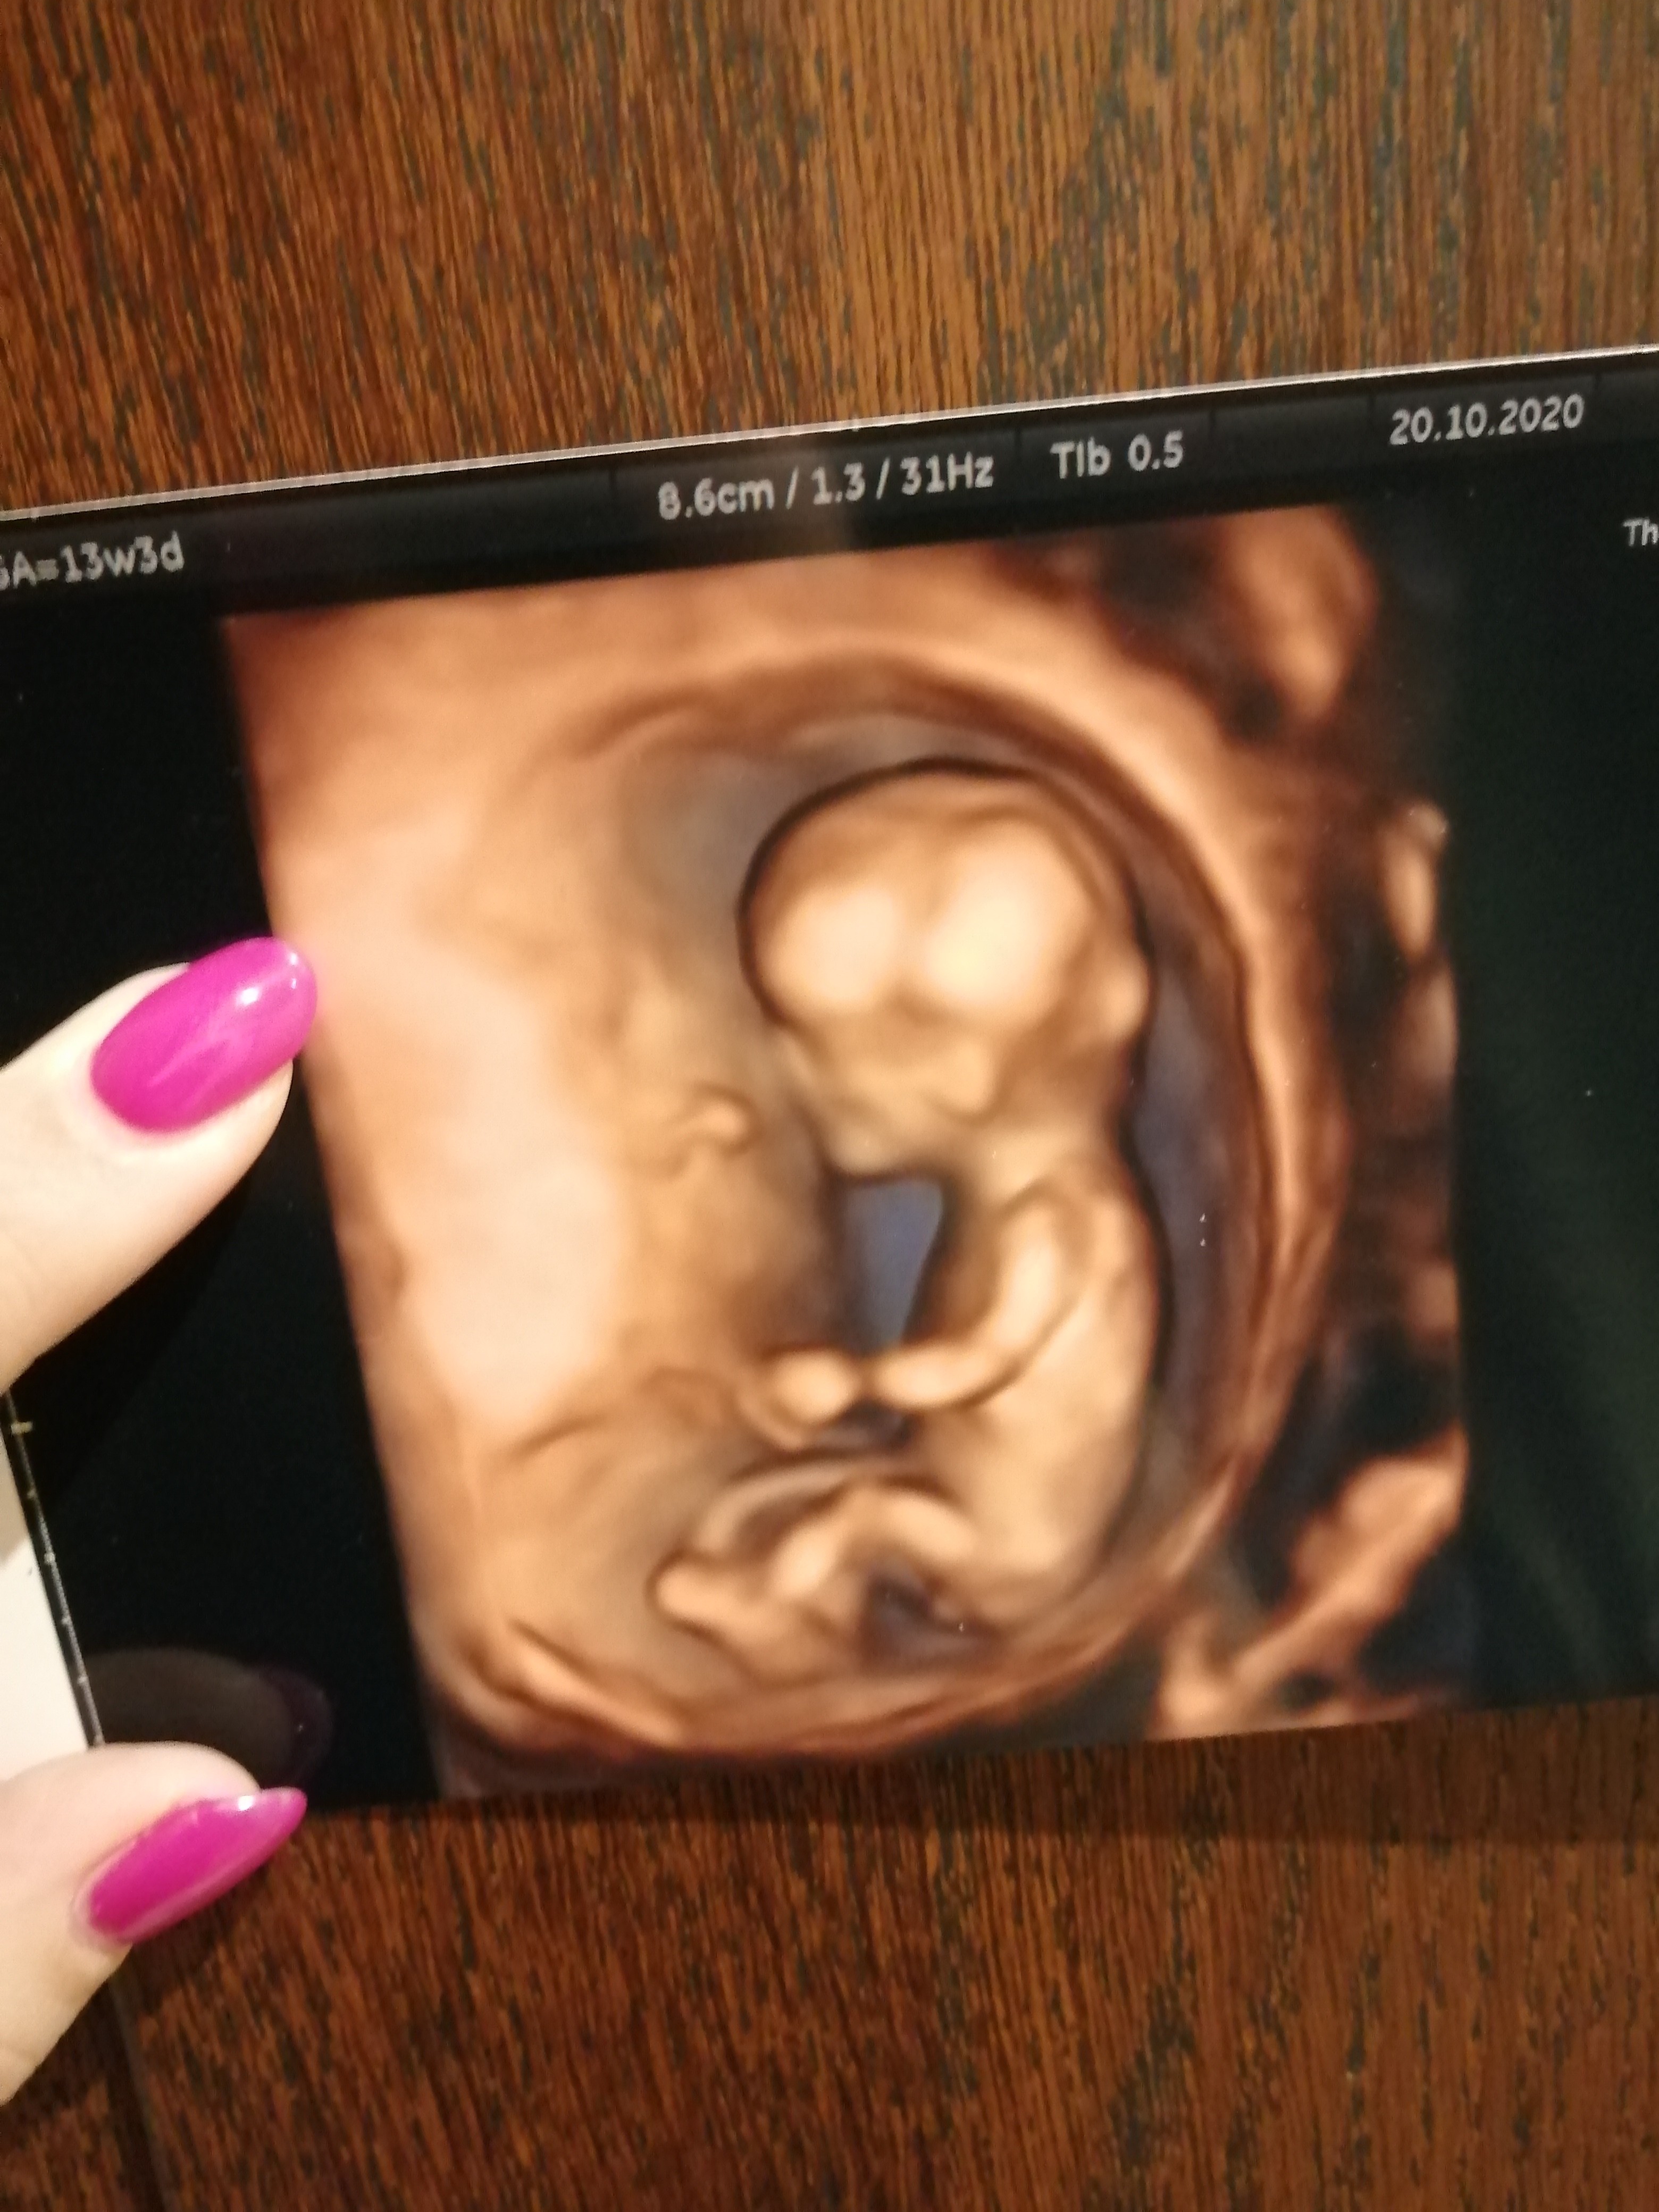

Hej dziewczyny. Kogo widzicie na zdjeciu?

Załączniki

• IMG_20201020_201238.jpg

IMG_20201020_201238.jpg

1,4 MB · Wyświetleń: 126